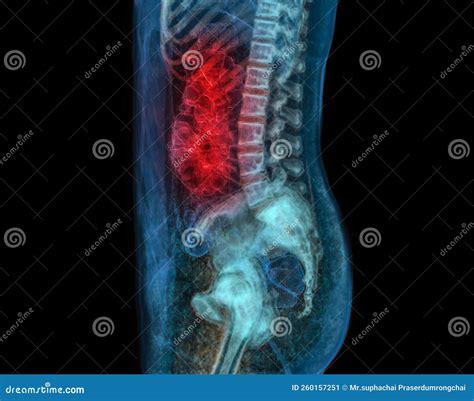

At its core, Ct Scan Colonography is a specialized radiological imaging test that produces 2D and 3D images of the large intestine. Unlike a standard colonoscopy, which involves physical exploration of the bowel, this procedure relies on computed tomography (CT) to create a detailed internal map. The process requires the patient’s colon to be inflated with air or carbon dioxide to ensure the walls of the bowel are fully distended, which allows the CT scanner to capture clear, unobstructed views of the lining.

• Inflation: A thin, small tube is placed just inside the rectum. Through this tube, air or carbon dioxide is gently pumped to inflate the colon, ensuring the entire surface is visible to the scanner.

• Imaging: The patient will hold their breath for brief intervals while the scanner captures high-resolution images, usually in two positions: once while lying on their back and once while lying on their stomach (or side).